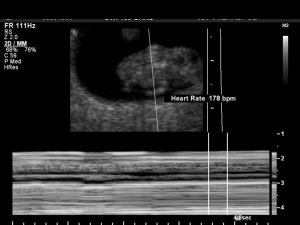

178 beats per minute. 178 tiny reassurances that the human your body is growing is healthy and viable.

The swoosh beating sound filled the tiny, but comfortable, ultrasound room and I breathed a sigh of relief. Just one baby with one strong heartbeat. The two confirmations I was looking for that day.